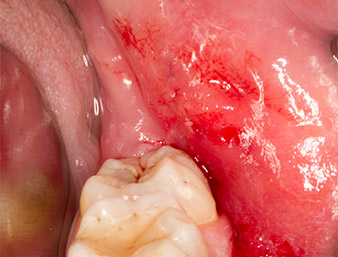

Das Gewebe über dem Wurzelrest war nicht vollständig verknöchert und bestand zu einem großen Teil aus entzündlich verändertem Granulationsgewebe (Abb. 4).

Granulationsgewebe

Abb. 4: Zwei Langenbeck-Haken und ein Raspatorium nach Prichard stellen das OP-Feld dar. Granulationsgewebe der unvollständig abgeheilten ersten Osteotomie ist zu erkennen.